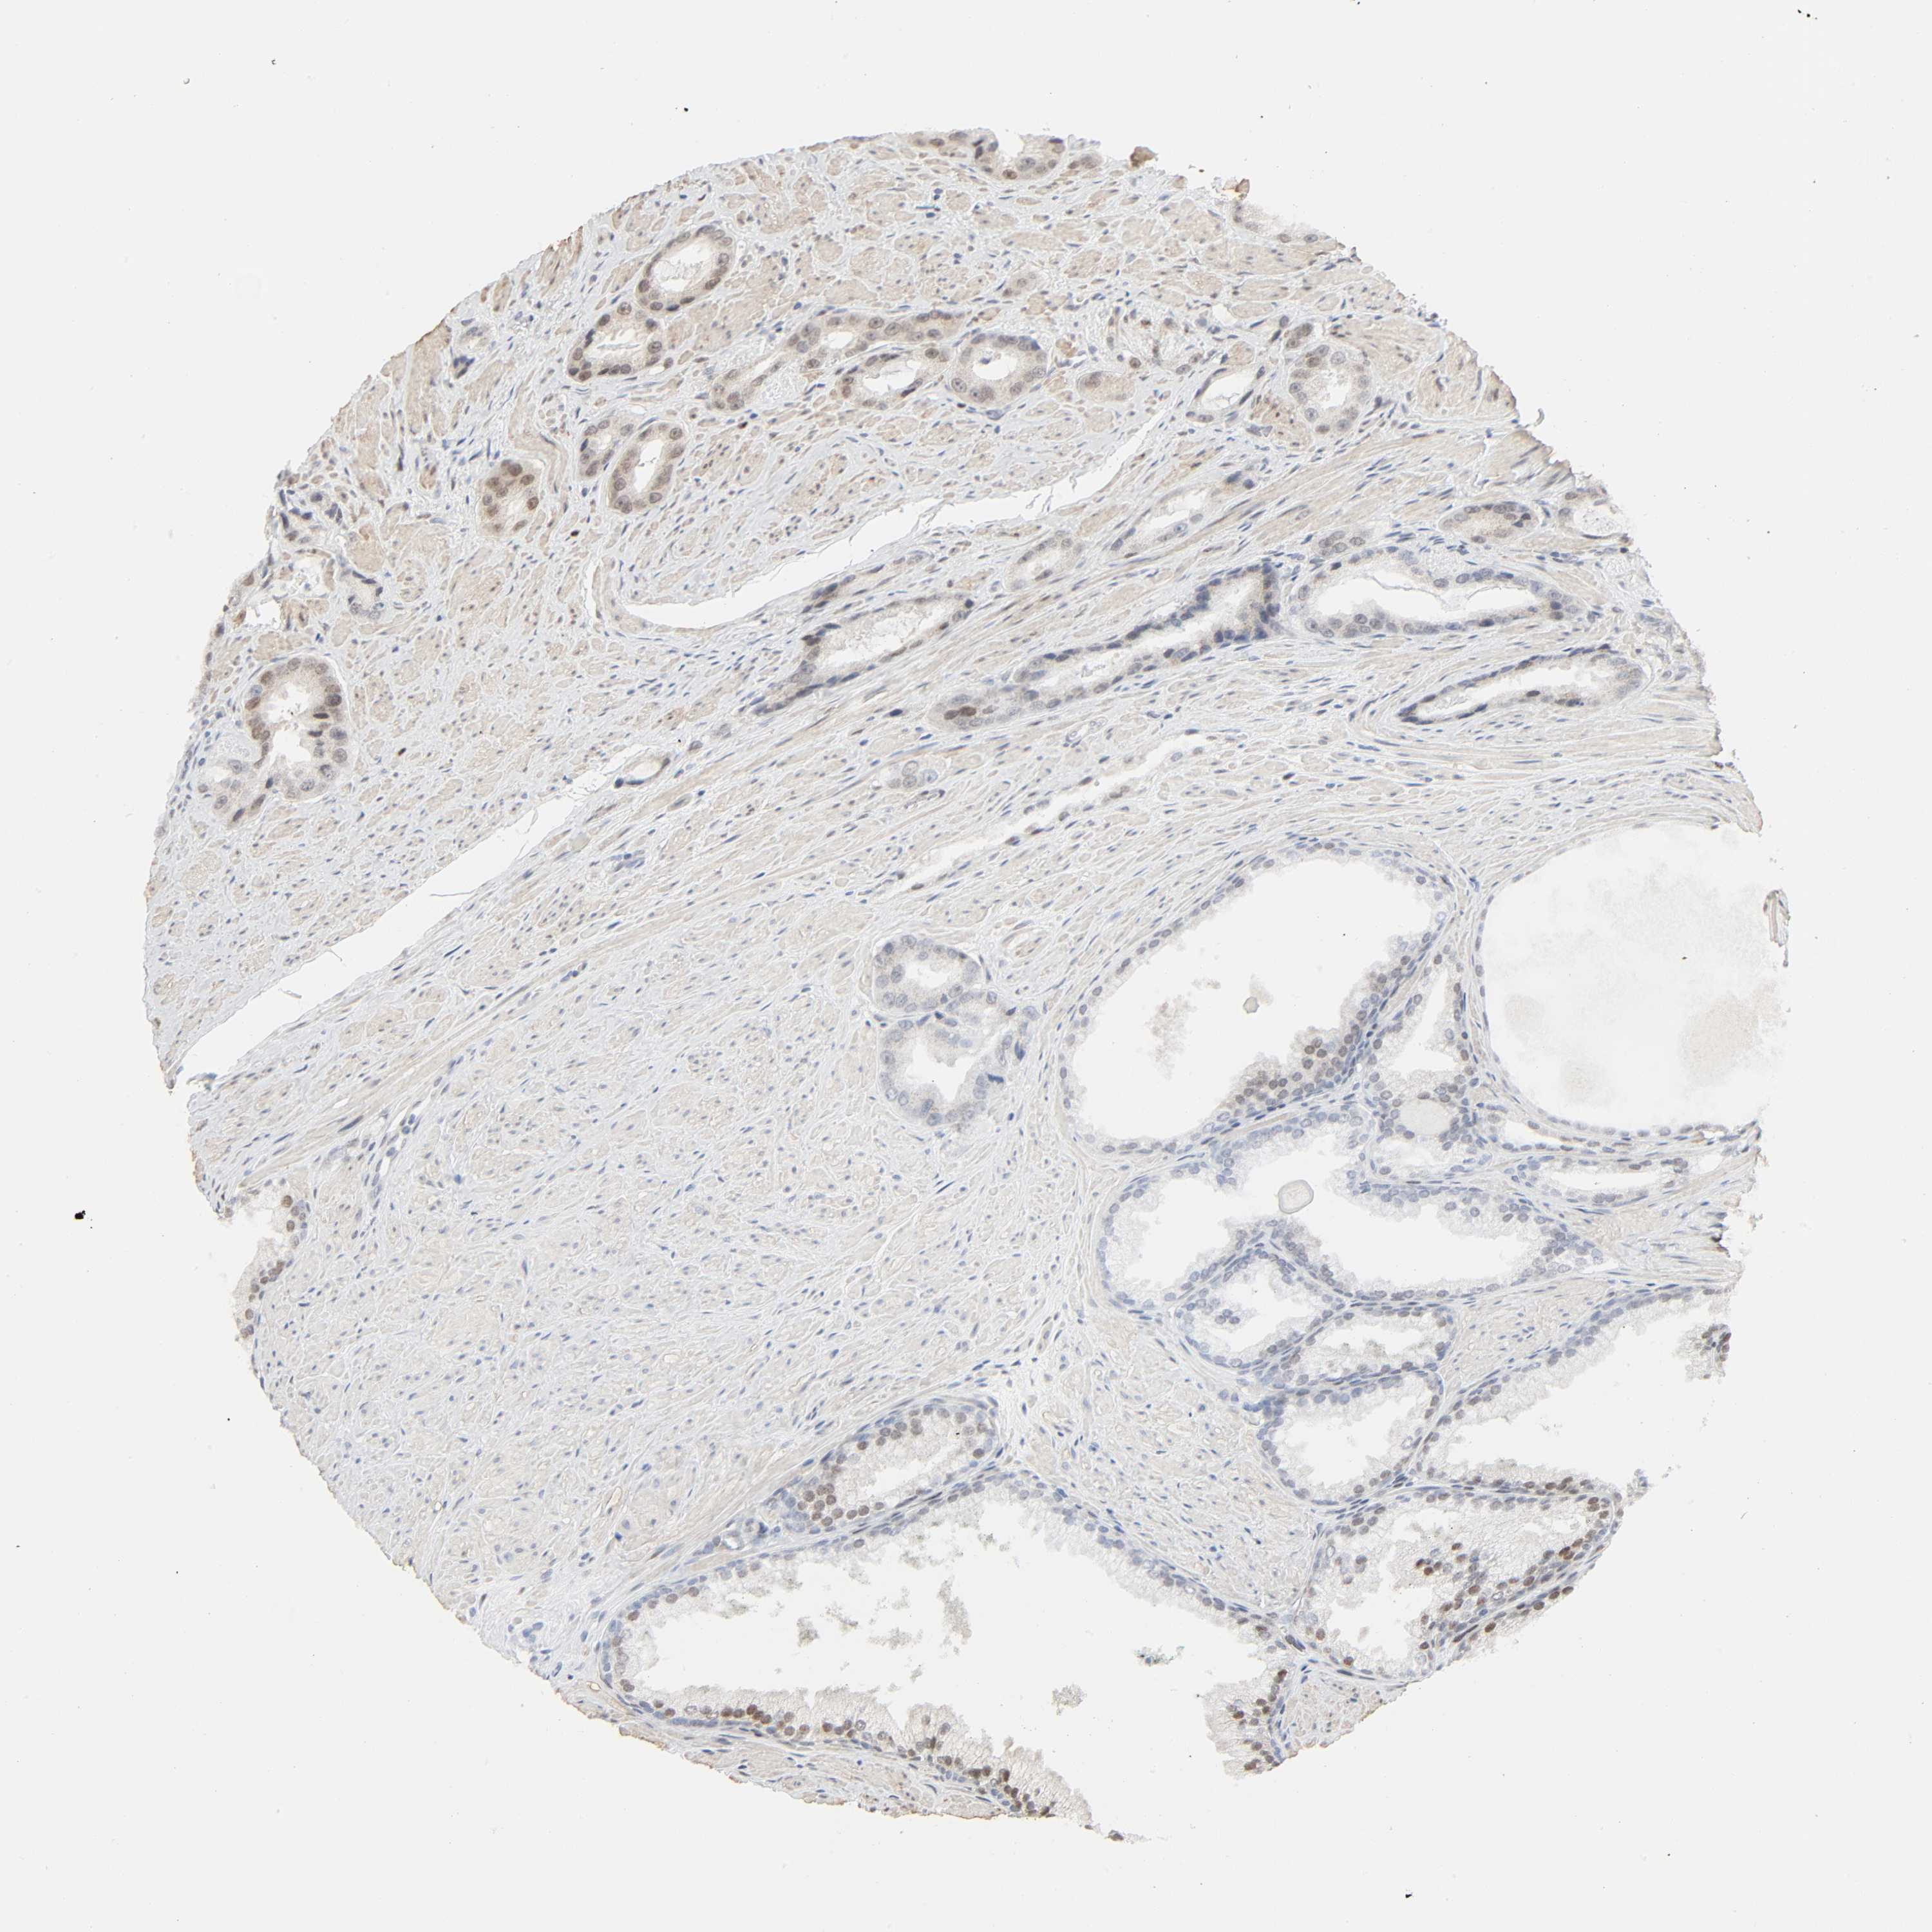

PROSTATE CANCER - Protein expressioni

A mouse-over function shows sample information and annotation data. Click on an image to view it in a full screen mode. Samples can be filtered based on level of antibody staining by selecting one or several of the following categories: high, medium, low and not detected. The assay and annotation is described here.

Antibody stainingi

Antibody staining in the annotated cell types in the current human tissue is reported as not detected, low, medium, or high, based on conventional immunohistochemistry profiling in selected tissues. This score is based on the combination of the staining intensity and fraction of stained cells.

Each image is clickable and will lead to virtual microscopy that enables deeper exploration of all samples and also displays staining intensity scores, fraction scores and subcellular localization as well as patient and tissue information for each sample.

Antibody CAB004540

Adenocarcinoma, Medium grade

Adenocarcinoma, High grade

Adenocarcinoma, Low grade